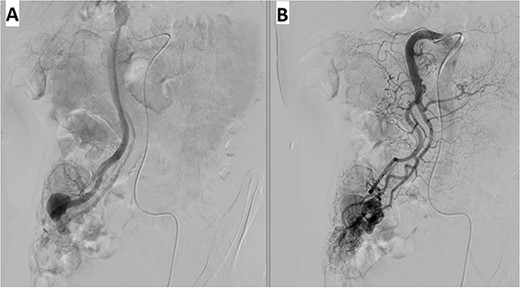

A 57-year-old male patient with a history of hypertension was referred to our hospital for multiple episodes of painless bloody stools for 2 weeks. No gastrointestinal symptoms were observed, such as abdominal pain, nausea or vomiting. A digital rectal examination showed bright red blood. On admission, laboratory evaluation revealed mild anemia with hemoglobin of 103 g/dL. Other than that, there were no other abnormalities. Lower and upper gastrointestinal endoscopy was performed, but the cause of the bleeding could not be identified. Due to the signs and symptoms of ongoing bleeding, we decided to perform imaging tests to make a diagnosis. Abdominal contrast-enhanced computed tomography (CT) revealed a thickened appendix (17 mm in diameter and wall thickening 6.4 mm) without signs of inflammation and images of vascular proliferation and dilated vein around the appendix (Fig. 1). An angiography was performed and demonstrated the AVM of the appendicular artery and vein (Fig. 2).

Contrast-enhanced abdominal CT showed a thickened appendix without signs of inflammation and images of vascular proliferation and dilated veins around the appendix.